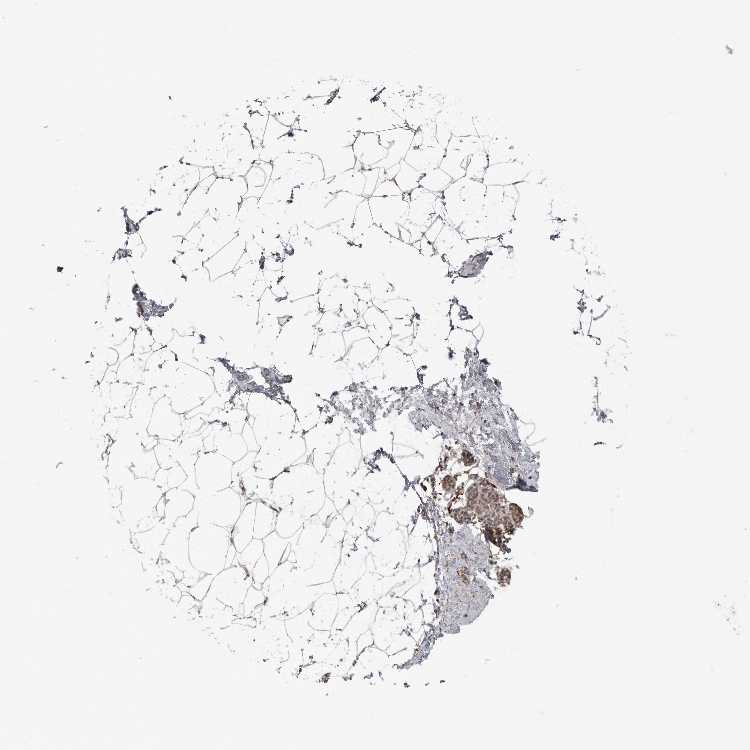

BREAST - Antibody stainingi

Antibody staining in the annotated cell types in the current human tissue is reported as not detected, low, medium, or high, based on conventional immunohistochemistry profiling in selected tissues. This score is based on the combination of the staining intensity and fraction of stained cells.

Each image is clickable and will lead to virtual microscopy that enables deeper exploration of all samples and also displays staining intensity scores, fraction scores and subcellular localization as well as patient and tissue information for each sample.

Antibody HPA027468Antibody HPA028668

Adipocytes LowNot detected

Glandular cells LowHigh

Myoepithelial cells LowNot detected